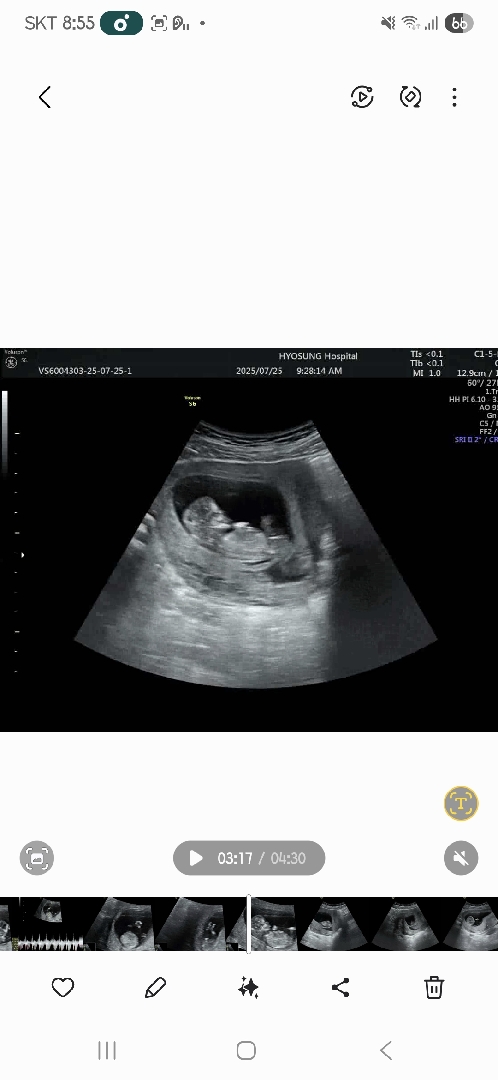

저번주에 1차기형아검사 통과했는데요! 다만 피고임이 있다고 유산방지주사(돌주사)맞구 가라고해서 맞았어요. 지지난주에 서브병원에서 봣을때도 피고임 있다구하셨는데 계속있다고 하니 신경이 쓰이네요 ㅠ 전백수라 서있는일이 크게 많지두 않은데 말이죠 ㅠ 한달뒤에 이제 진료보는데 큰일아니니 이때보는거겠죠,,,. 새벽에 배두 아파서 깬적이있구 쥐어짜는것같은 고통도있엇구요... 토끼응아처럼 나오는거봐선 변비라서 그런거같기두한데 이러신분들 많나요??ㅠㅠ

피고임은 임산부의 30퍼가 있을 정도로 흔하니 걱정은 말라셨고, 오른쪽 아랫배가 찢어지듯?땡기듯? 너ㅓ무 아파서 잠에서 깨고 무서워서 병원 오픈런 햇는데 문제 없고 애기 잘 크고 있다고 했어요! 이것저것 찾아보니 자궁 인대가 늘어날때 다들 이시기에 이만큼 아프다고 하더라구요Ĭ^Ĭ